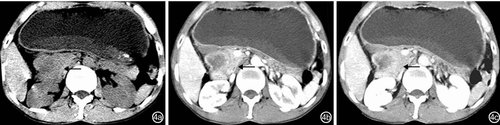

良性间质瘤患者CT检查主要表现为局限性中重度肠壁增厚,肠腔内、肠壁内或浆膜下软组织包块病变肠壁明显不均匀强化,呈现“环靶征”(图2);肠外主要表现为肠套叠、肠梗阻征象:肠管扩张、积液、积气。(点击图片可查看原图)

图2 空肠良性间质瘤(肠道内壁间质瘤继发空肠肠套叠)患者CT检查特征:2a:平扫空肠内壁呈结节状不均匀性增厚(←),密度不均匀;2b:动脉期局部肠壁明显不均匀强化,呈“环靶征”(←);2c:静脉期病变近段肠壁重度增厚(→)

恶性间质瘤患者CT检查表现为局限性或节段性中重度肠壁不均匀性增厚,肠腔内、肠壁内或浆膜下软组织包块、病变中心坏死液化,病变肠壁明显不均匀强化(图3);肠外主要表现为肠系膜和大网膜转移、肝转移。(点击图片可查看原图)

图3 空肠恶性间质瘤患者CT检查特征:肠壁局限性不均匀性增厚,内见坏死液化灶(→),腹腔积液(↓)和肠系膜增厚(↑) 3a:平扫肠壁局限性不均匀性增厚、边界不清(←);3b:动脉期局部肠壁明显不均匀强化;3c:静脉期肠壁强化程度减弱